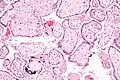

![]() Микрофотография плацентарной инфекции (плацентарный ЦМВ) | |

Микрофотография цитомегаловирусного плацентита.